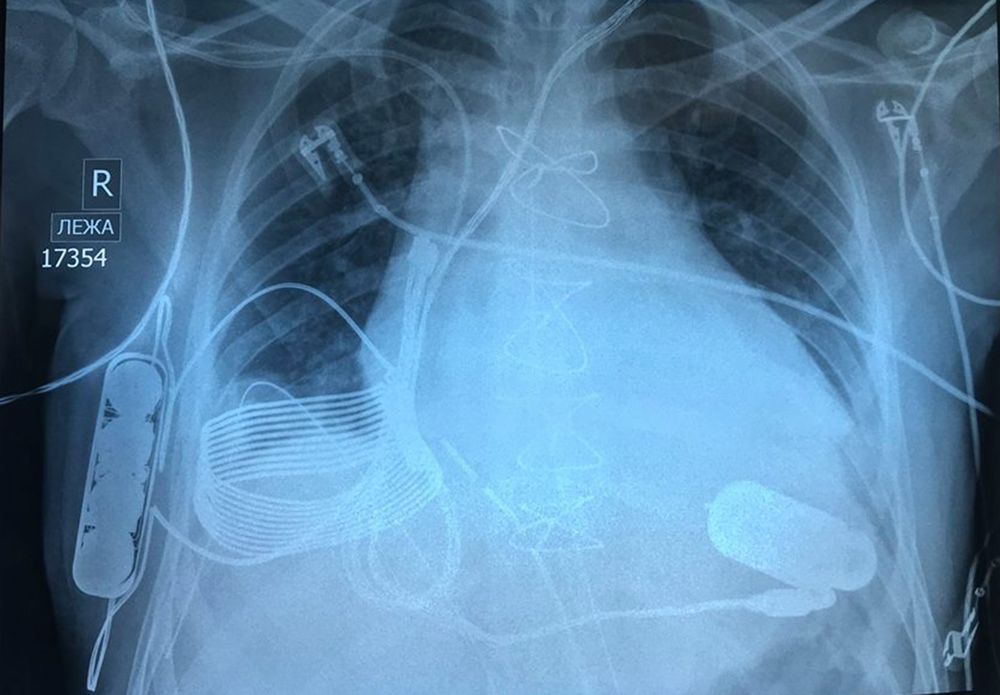

Уникальные устройства спасли бесчисленное количество жизней. Сейчас технология вышла на новый уровень: ученым впервые удалось вживить в грудь 24-летнего мужчины из Казахстана, страдающего от сердечной недостаточности последней стадии, устройство, которое заряжается беспроводным способом.

Операция была проведена в Национальном исследовательском центре кардиохирургии в Астане, говорится в сообщении израильской технологической компании Leviticus Cardio.

Новое устройство не нуждается в проводе питания благодаря системе зарядки, созданной израильской технологической компанией Leviticus Cardio. Система состоит из индуктивной катушки приемника, аккумулятора внутреннего контроллера — все они имплантированы в грудь пациента. От одного заряда устройство может проработать около восьми часов.